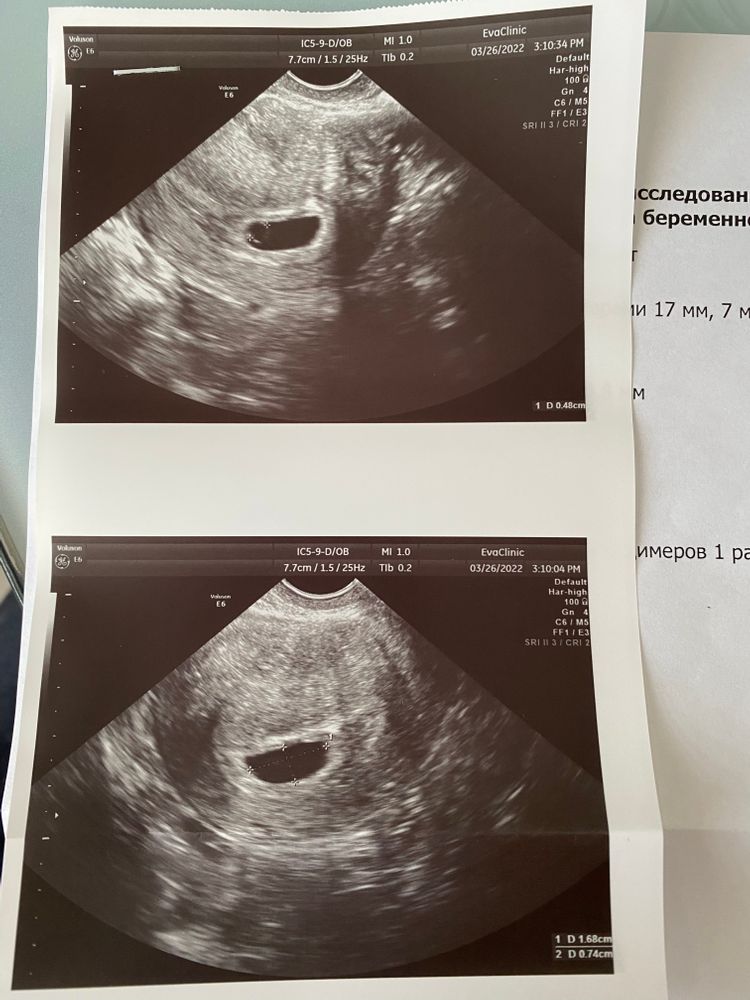

Девочки, вчера была на узи на 24 дпп, переносили 5-дневочку, врач сказала все хорошо, гематом и отслоек нет, ПЯ 13 мм, желточный мешочек 4.8 мм, эмбрион ещё не визуализируется, должен появиться через 7-8 дней. А я тут читаю , что многих уже был и эмбрион и сердцебиение на 24 дпп. У кого не было , на какой дпп появился эмбриончик?